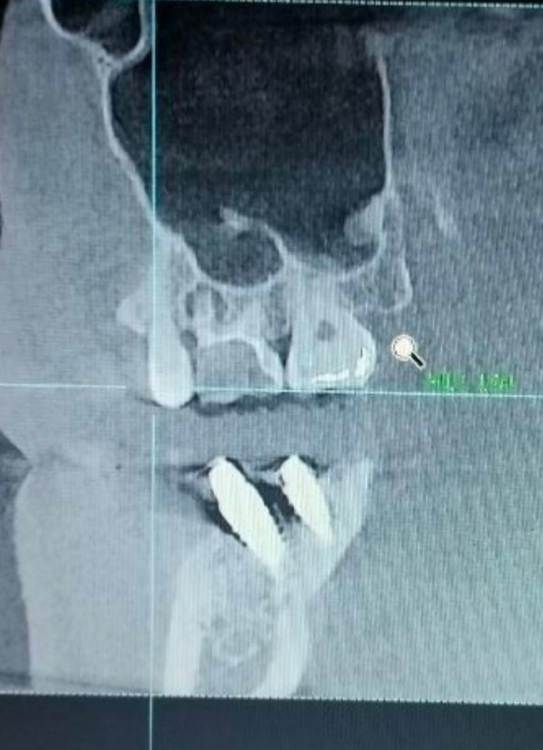

Здравствуйте ! Ситуация следующая - 6 сверху коронка с резекцией , долгое время осталась без антагониста , соотвественно выдвинулась (это уже мое предположение) . Чтобы спасти зуб , доктор принял решение повести гемисекцию корня . После - осталась рассечена десна .. Доктор говорит десна заживет , но визуал мягко говоря напрягает , так как при улыбке у меня это все видно ..

Фото 7,8 - Также была проведена резекция кисты 5 зуба снизу , с коронкой , и установка 7 импланта в качестве антагониста верхней 7 . Одной операцией . Коронка оголилась , швы сняли на 3 день .. доктор также утверждает что в дальнейшем будет все хорошо , зарастет . Также очень смешает внешний вид десны , десна стала волной даже на 6 ..